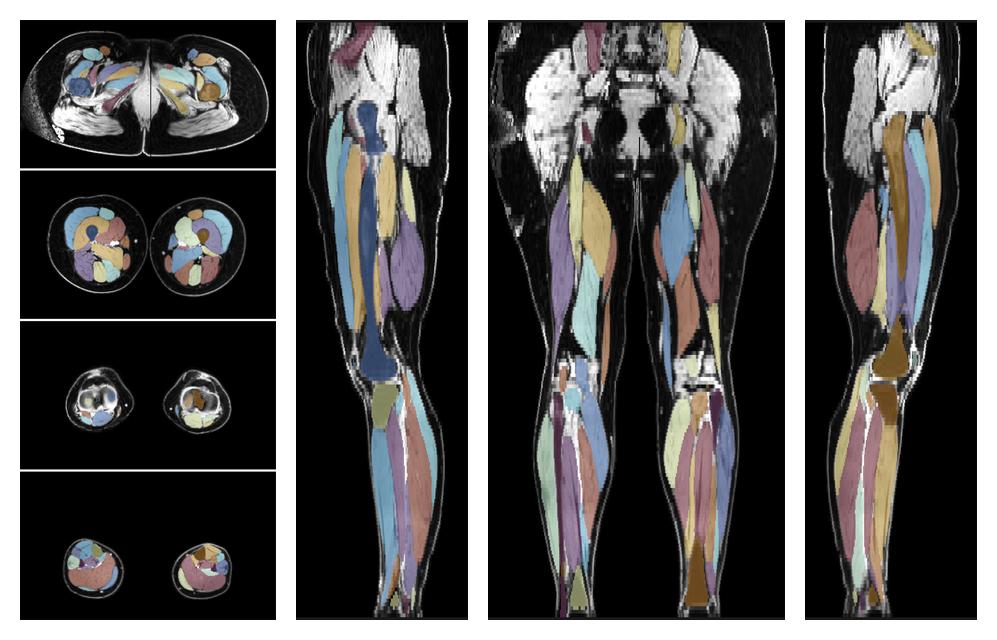

• Automated muscle and bone segmentation.

Overlay of automated muscle segmentation labels on dixon water image.